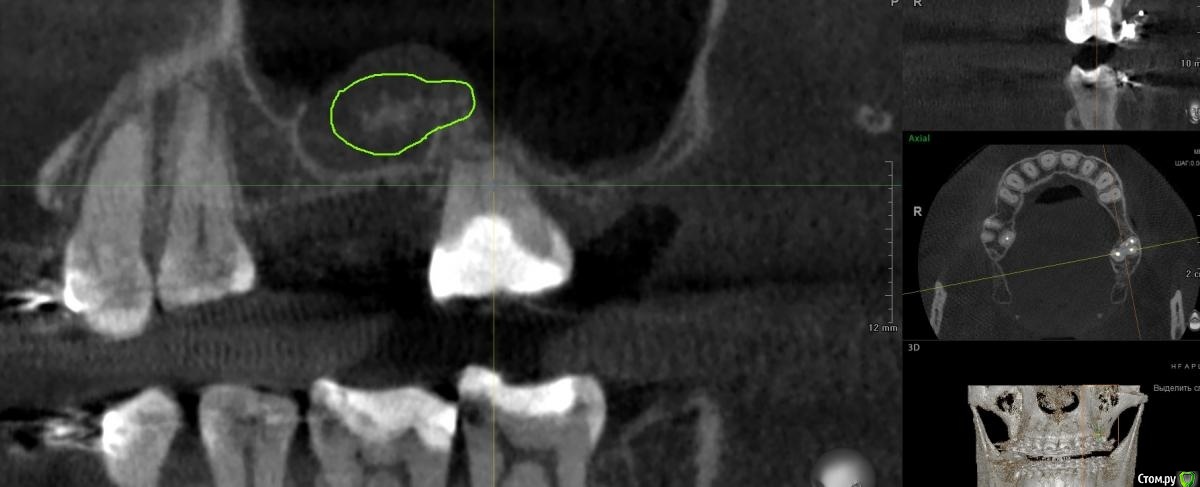

Doctor Vlad Опубликовано 11 марта, 2021 Поделиться Опубликовано 11 марта, 2021 Чтобы не плодить темы. Похоже, но с вкраплениями, мед щечный не обтурирован до верхушки, думаю как то связано. А может и нет. Планирую имплантацию с синусом открытым. Ссылка на комментарий

shy Опубликовано 11 марта, 2021 Поделиться Опубликовано 11 марта, 2021 Чтобы не плодить темы. Похоже, но с вкраплениями, мед щечный не обтурирован до верхушки, думаю как то связано. А может и нет. Планирую имплантацию с синусом открытым. это оссификаты , ничего не делать , плановый ОСЛ Ссылка на комментарий

Doctor Vlad Опубликовано 11 марта, 2021 Поделиться Опубликовано 11 марта, 2021 это оссификаты , ничего не делать , плановый ОСЛи не смущает очаг инфекции в области периапикальных тканей 27? да образование в синусе не над ним, но все рядом Ссылка на комментарий

annda Опубликовано 12 марта, 2021 Поделиться Опубликовано 12 марта, 2021 (изменено) А это может быть аспергеллиоз? Изменено 12 марта, 2021 пользователем annda 1 Ссылка на комментарий

wladdX Опубликовано 12 марта, 2021 Поделиться Опубликовано 12 марта, 2021 А это может быть аспергеллиоз?А очень даже может быть Ссылка на комментарий